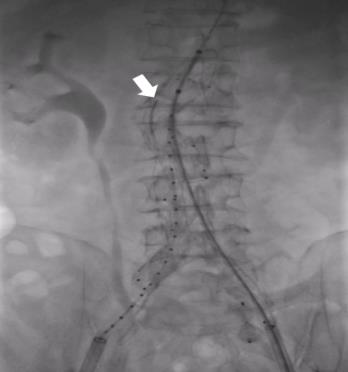

• Clinical application of three-dimensional visualization technology in assessing the spatial configuration of major hepatic vessels and liver lobar volume distribution

2026, 35(1):124-140. DOI: 10.7659/j.issn.1005-6947.250635

Abstract (93) HTML (137) PDF 3.82 M (171) Comment (0) Favorites

Abstract:Background and Aims The hepatic vascular and biliary systems exhibit substantial anatomical variability and complex spatial relationships, posing challenges for precise surgical planning based on conventional two-dimensional imaging. This study aimed to evaluate the clinical value of three-dimensional visualization in characterizing the spatial architecture of hepatic vasculature and bile ducts and to explore its association with hepatic volumetric distribution.Methods A total of 610 living liver donors and 158 patients with bile duct dilatation were retrospectively analyzed. Three-dimensional models of the hepatic artery, portal vein, hepatic veins, and bile ducts were reconstructed from contrast-enhanced CT images. Vascular and biliary anatomical patterns, spatial relationships, and their correlations with hepatic lobe and segmental volumes were systematically assessed.Results Three-dimensional visualization enabled intuitive and comprehensive depiction of hepatic vascular and biliary anatomy. Distinct portal vein configurations were associated with significant differences in regional liver volume distribution, with an increased proportion of the right posterior lobe observed in patients with specific portal vein branching patterns. The presence of an inferior right hepatic vein with a diameter ≥5 mm was also associated with a larger right posterior lobe volume. Analyses of extrahepatic and intrahepatic spatial relationships revealed relatively consistent positional patterns between the right hepatic artery, portal vein, and bile ducts, and a significant correlation was observed between the spatial courses of the right hepatic artery and the right posterior bile duct.Conclusion Three-dimensional visualization provides accurate preoperative assessment of hepatic vascular and biliary anatomy and clarifies complex spatial relationships and their volumetric implications. This technique offers critical anatomical support for precision hepatobiliary surgery and liver transplantation.